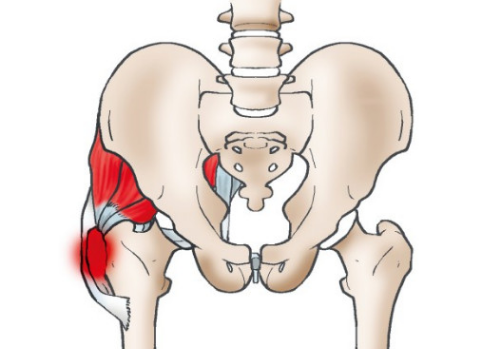

고관절 통증 원인 ① 좌골신경통

좌골신경통은 고관절 통증을 유발할 수 있습니다. 이는 좌골신경 자극 또는 염증으로 인해 다리에 통증이 나타나며, 이러한 통증이 고관절에까지 영향을 미칠 수 있기 때문입니다. 좌골신경증에 따르면, 통증은 허리에서 시작하여 고관절을 거쳐 발바닥까지 뻗을 수 있습니다.

고관절 통증 원인 ③ 건염

고관절 통증의 일반적인 원인 중 하나는 건염입니다. 건염은 주로 과도한 운동으로 인해 발생하는 경우가 많습니다.